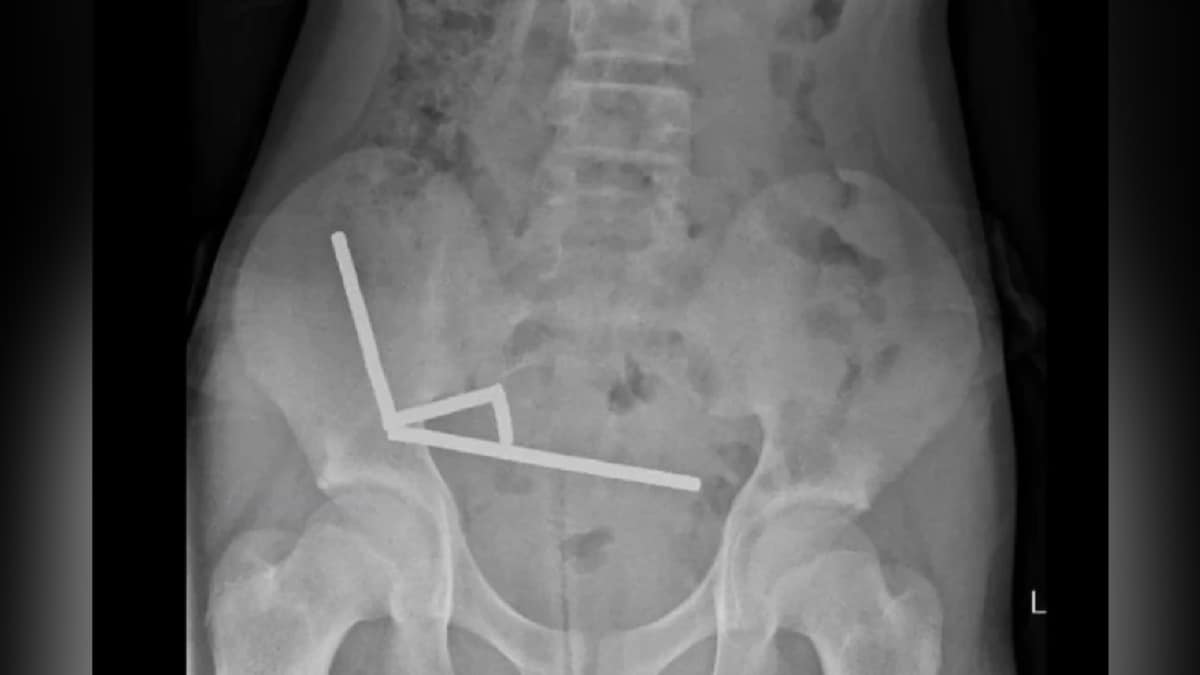

They discovered that the magnets had joined together to form four chains inside his intestines. According to the New Zealand Medical Journal , doctors said that boy had swallowed “approximately 80–100 5x2mm high-power neodymium magnets" a week prior to his hospitalization.